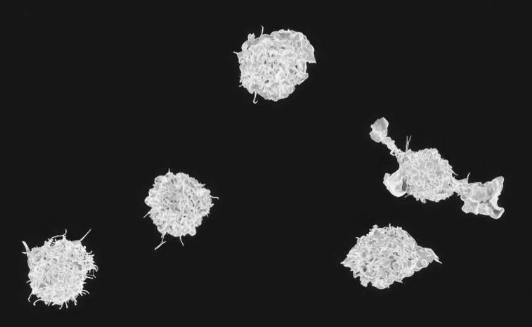

由达特茅斯盖塞尔医学院的研究人员领导并发表在《自然免疫学》上的一项新研究的结果揭示了巨噬细胞的关键功能差异,巨噬细胞是一种白细胞,在人体先天(一般)免疫系统中发挥着关键作用。对抗病原体的一线防御者。

巨噬细胞存在于所有组织中,已知其执行的功能包括包围和消化微生物、清除碎片和死亡细胞以及刺激其他免疫和非免疫细胞(包括那些参与适应性(专门)免疫的细胞)的活动。直到最近,组织驻留巨噬细胞被认为在很大程度上是同质的,也就是说,它们的组成和功能非常相似。